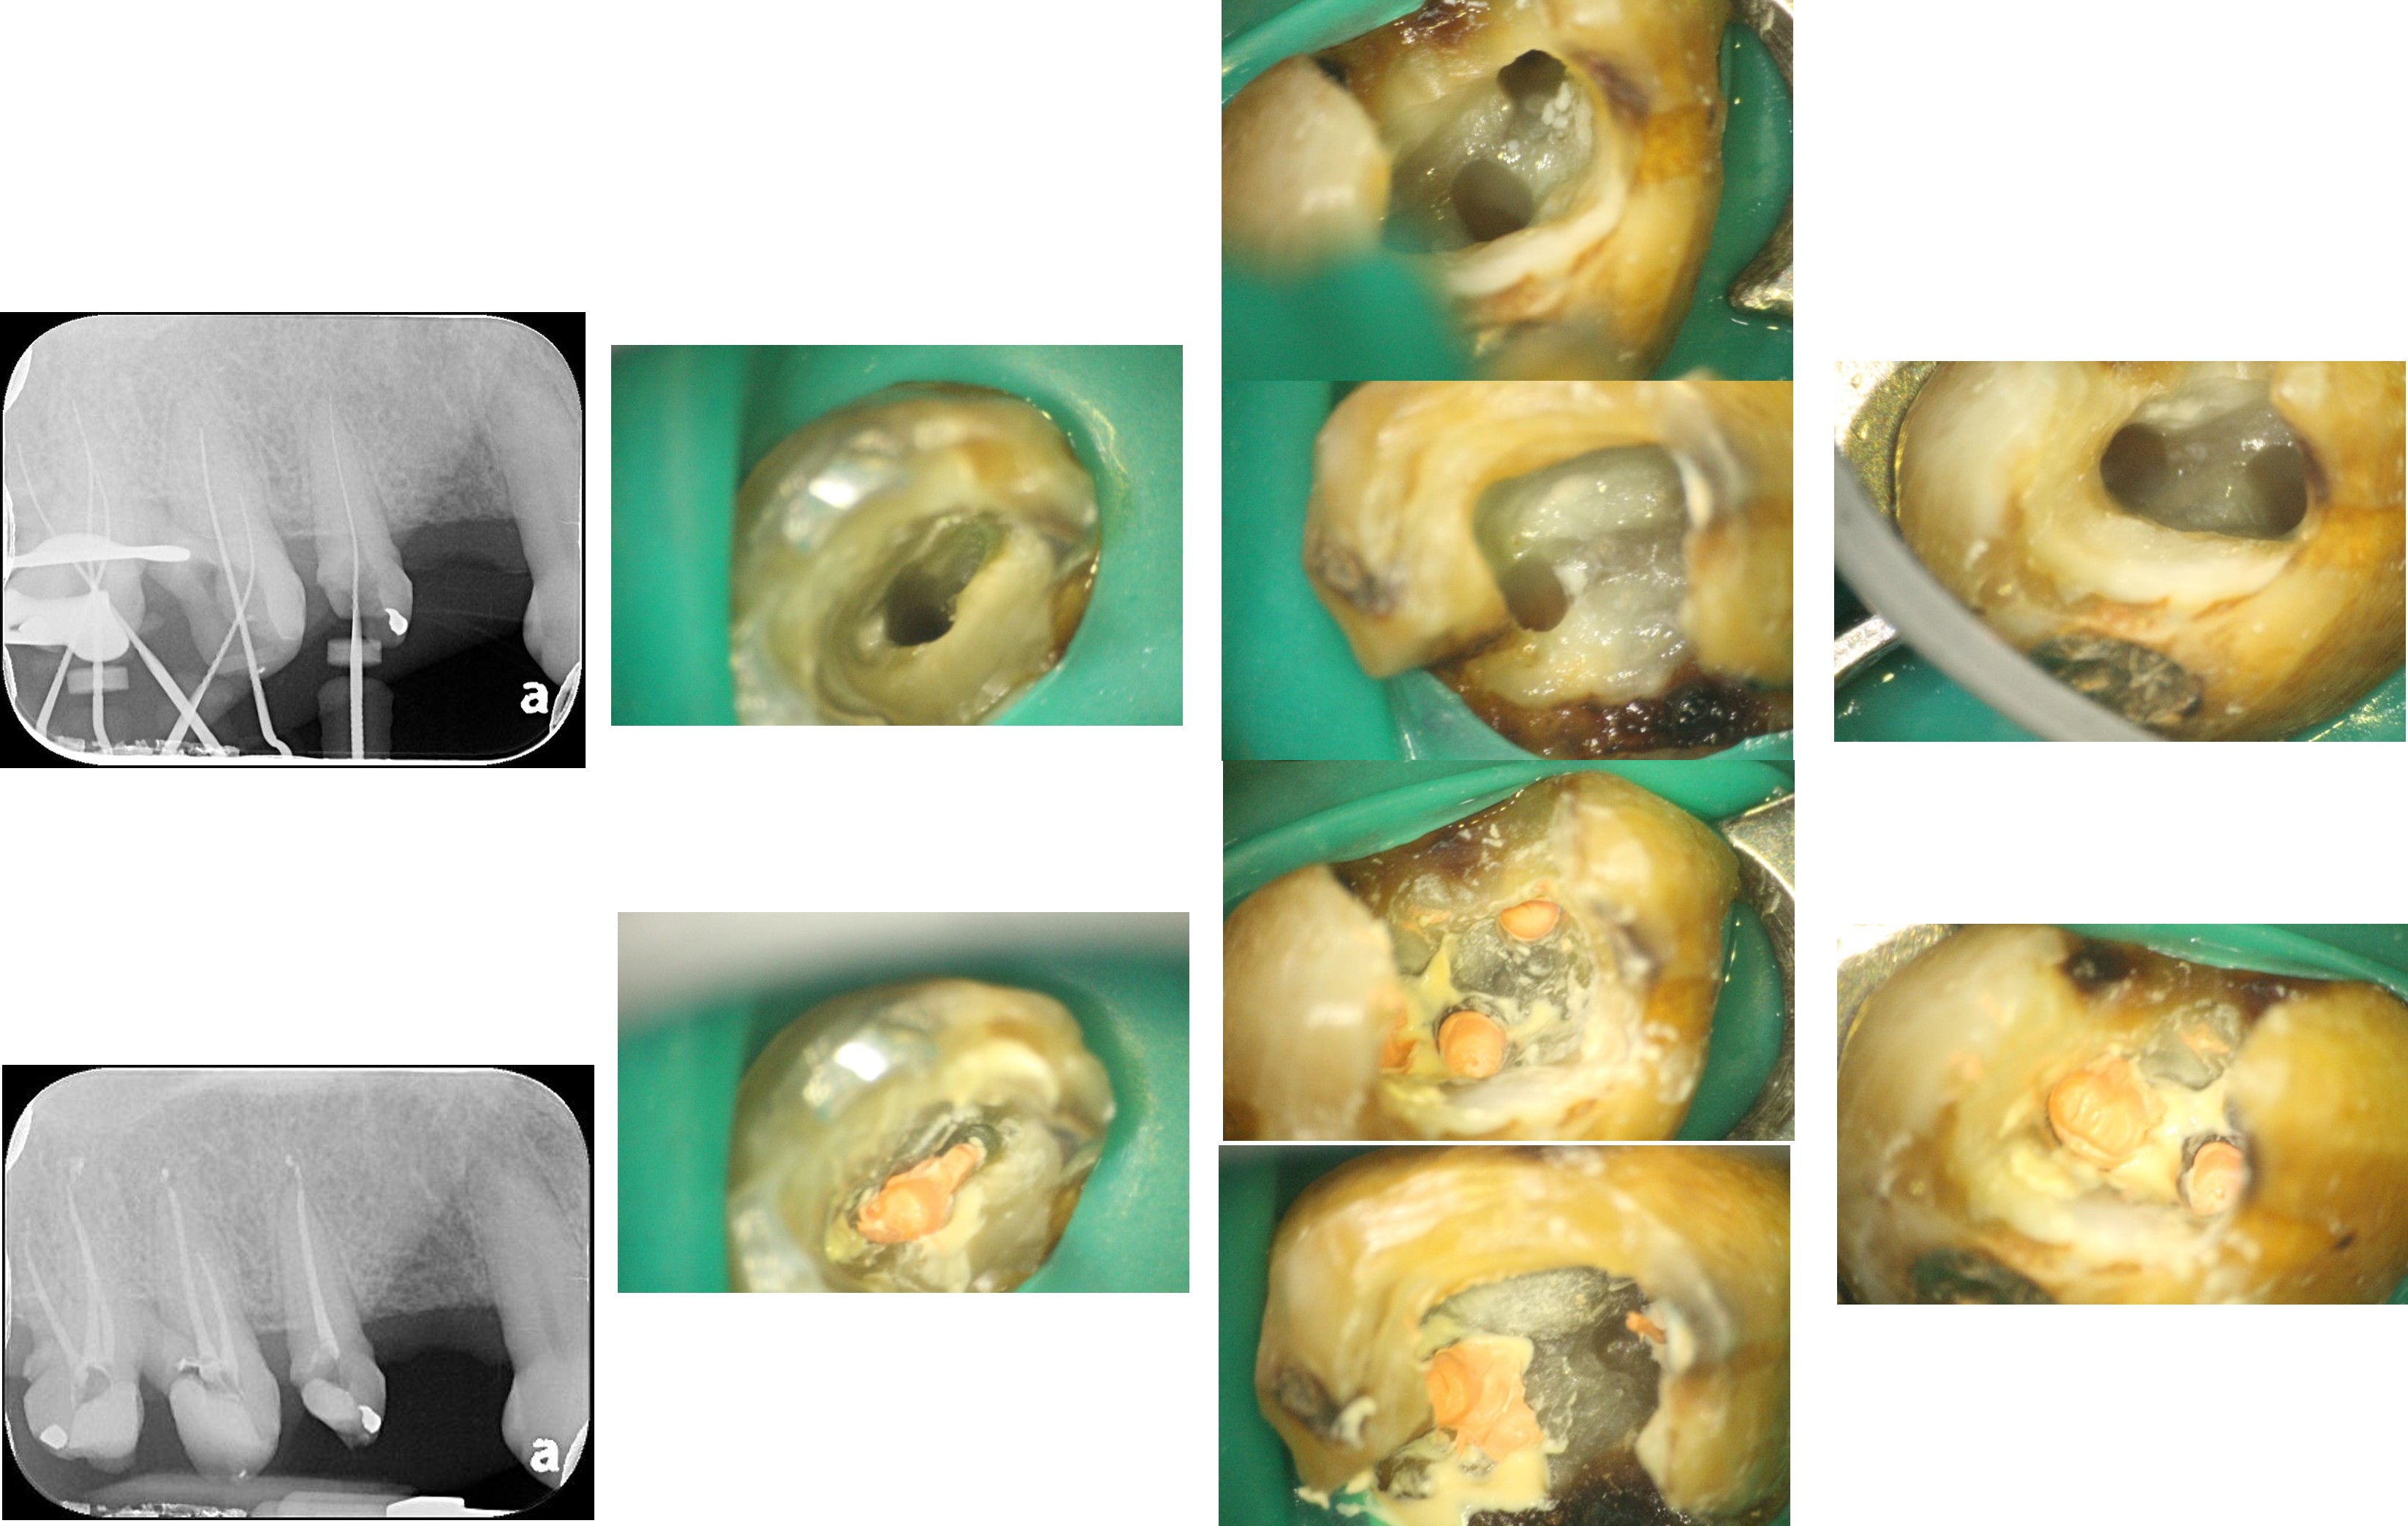

顯微根管重治療